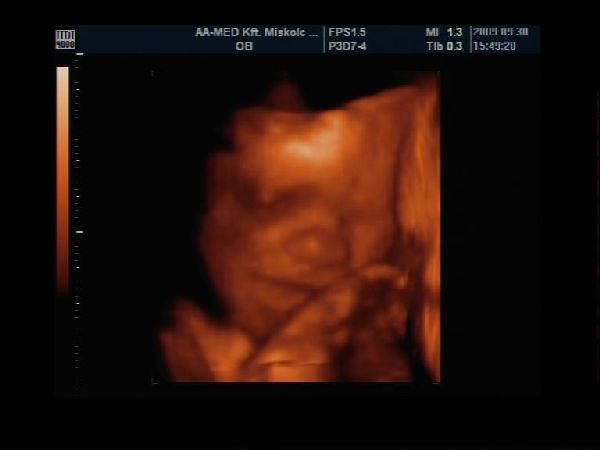

Kicsi fiam 27hetesen

Kép

Épp gondolkodik :)